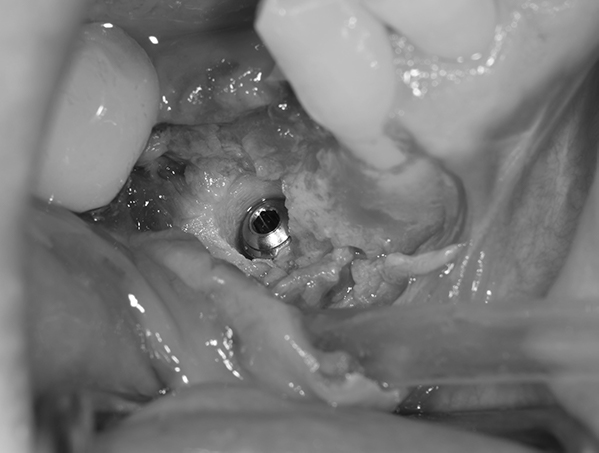

6ヶ月後再び歯茎を切り中の状態を確認。骨がしっかりできており、インプラント手術を行えることが分かると思う。 インプラントを埋めるための穴をあけて、インプラントを埋入した。

麻布十番歯科のインプラント手術の症例